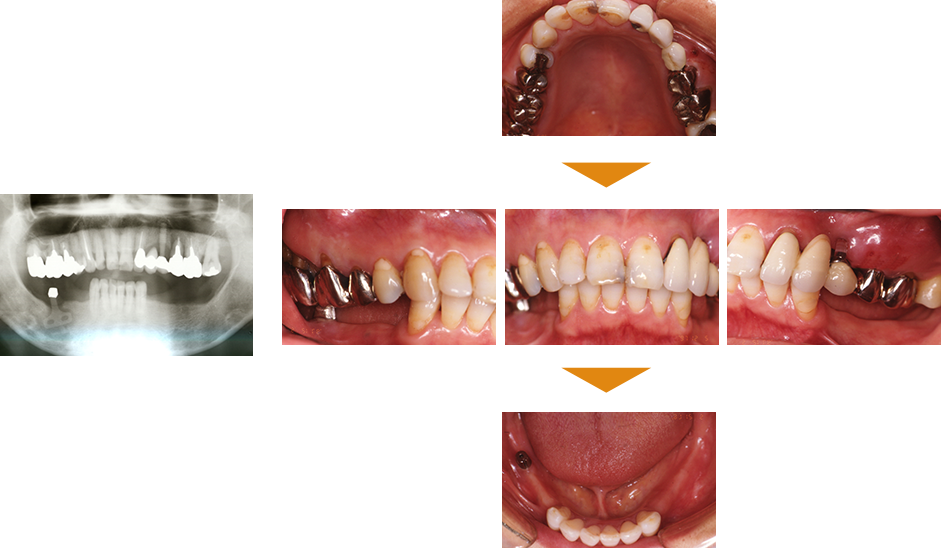

症例1

単独歯 インプラント即時荷重

|

| 治療期間 | 約4カ月 |

|---|

| 費用 |

インプラント治療費 400,000円

造骨費用 50,000円

合計 450,000円(税込) |

|---|

※状態により、骨補填等別途で費用が発生する場合もございます。